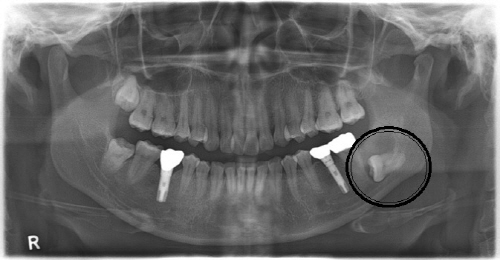

사랑니는 턱뼈가 작아진 현대인들의 구강 공간 부족으로 대부분 비뚫게 나거나 아예 턱뼈 속에 묻혀있는 경우가 많다.

보고에 의하면 완전히 잇몸뼈 안에 묻혀 있는 매복 사랑니의 약 3~23% 정도에서 물혹이나 종양 등 골치 아픈 합병증이 발생되는데, 턱뼈를 녹이고 상당히 크게 잠식할 때까지 증상이 없어 대부분 치과 치료 중 우연히 발견되거나 건강검진에서 발견되어 병원을 찾는 경우가 많다.

서울대학교치과병원 구강악안면외과 명훈 교수는 “잇몸 속에 묻혀있는 사랑니의 머리 부위 염증이 반복되면서 치아를 둘러싸고 있는 주머니가 물혹으로 발전하여 물이 차면서 커지게 되는데, 물혹이 커지면서 턱뼈를 녹이게 되고 이에 따른 합병증이 나타나게 되는 것”이라고 설명했다.

명훈 교수는 “사랑니와 물혹은 일반 치과에서 X-ray 검사로 간단히 진단할 수 있다. 20대에 사랑니가 나지 않았다고 해서 사랑니가 없다고 섣부르게 자가진단을 해서는 안 된다“고 조언했다.